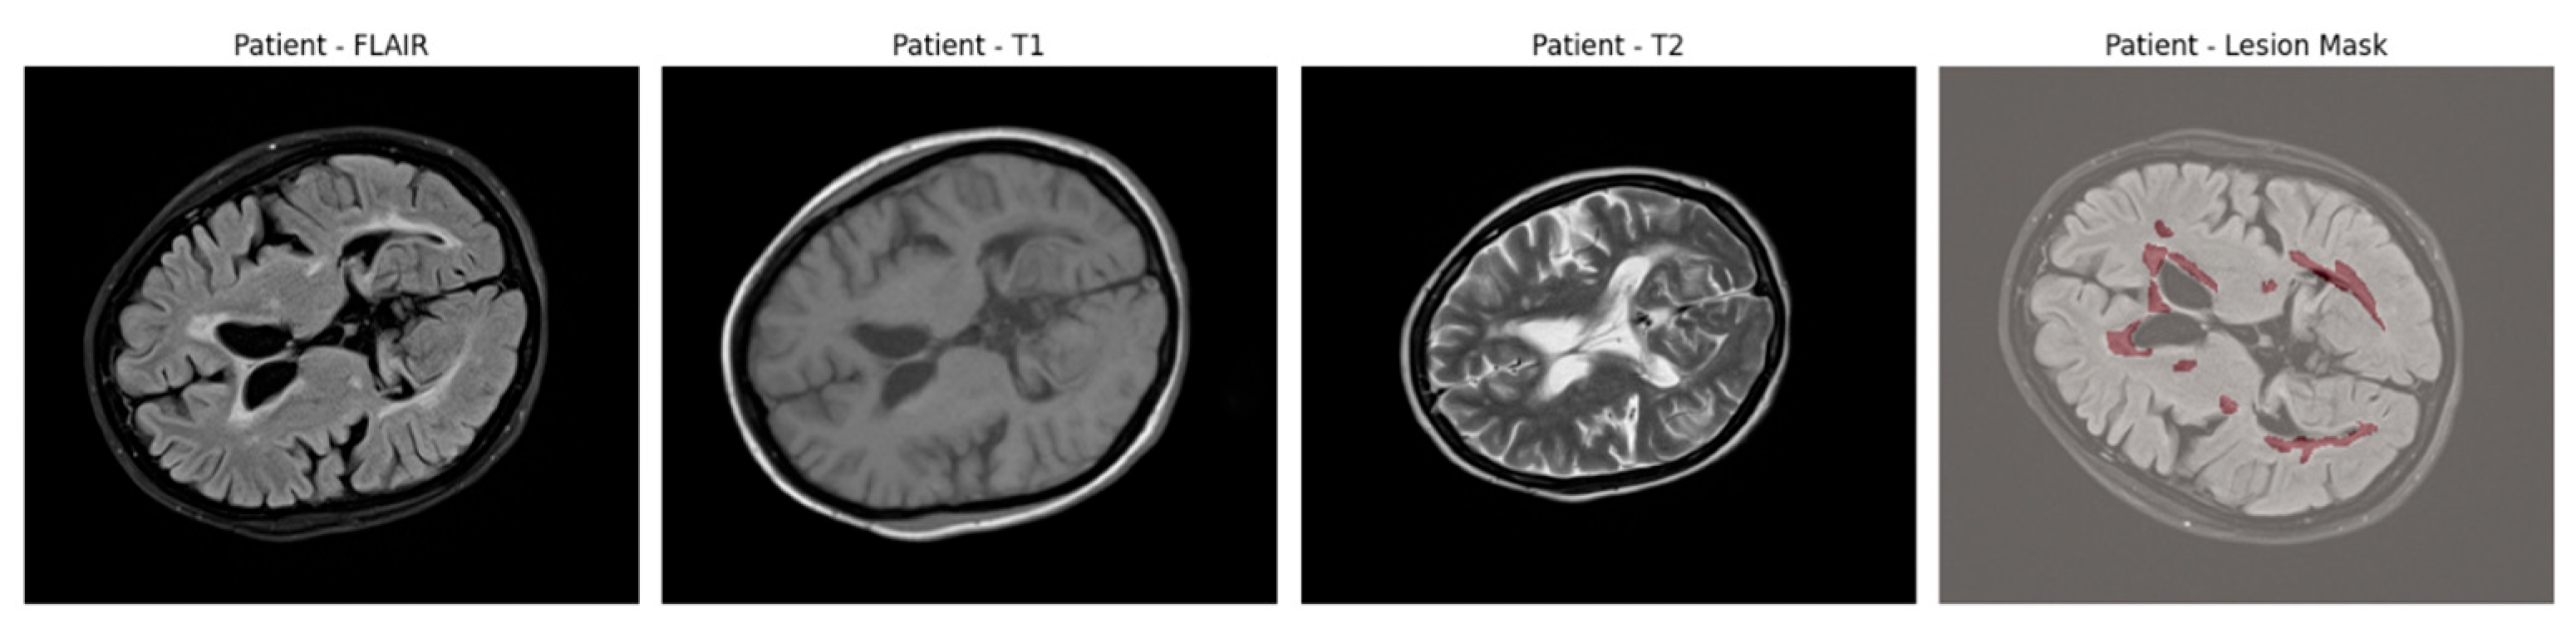

An example of axial slices from a representative patient is shown in Figure 1, showing the T1, T2, and FLAIR modalities alongside the corresponding lesion mask overlaid on the FLAIR scan. This highlights the multi-modal nature of the dataset and the spatial distribution of lesions across white matter regions.

Figure 1.

Axial brain slices from a representative MS patient showing the T1-weighted, T2-weighted, and FLAIR MRI sequences. The final panel overlays the expert-annotated lesion segmentation (in red) on the FLAIR image.